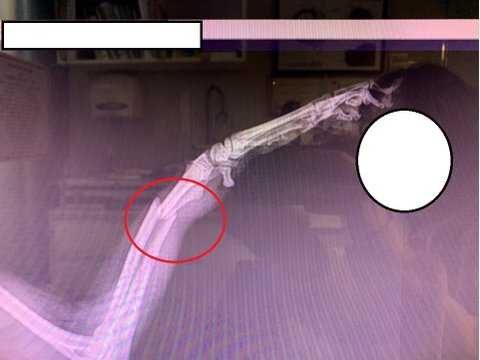

토이푸들이 목욕하는 도중에 뛰어내려서 앞다리를 절고 있다고 매장에 와달라고 하여

병원 원장님에게 상황설명을 드렸고 엑스레이 찍기 전에 강아지 진찰하면서 골절인거 같다고 말씀하셨습니다.

일단 엑스레이 찍고 왔는데 덜렁거리던 팔이 뿌러져서 덜렁거리던거였습니다.

병원비가 200만원이 나오고,

추후에도 장애가 있을수 있고(절뚝거리거나, 팔길이가 좀다를수있다고함)